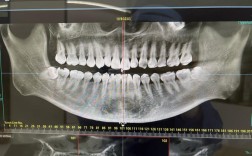

- 影像学定位:在头颅侧位片或锥形束CT(CBCT)三维重建图像中,N点表现为额骨鼻突与鼻骨之间的骨缝交点,位于鼻额缝的最前点,通常在侧位片上呈现为清晰的“V”形或“Y”形骨缝交叉影,需注意,影像学定位时应排除软组织(如鼻部脂肪垫、皮肤)的干扰,以骨性标志为准。